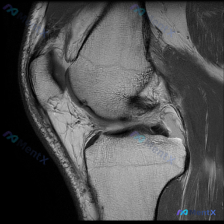

说软骨异常但单张MRI没看到异常?这个膝关节病例的影像分析思路值得捋捋

刚整理了一份有意思的膝关节MRI读片病例,临床提示观察到软骨异常,但单张T1加权矢状位影像却没看到明确异常,把分析思路整理出来和大家讨论。

这是一张膝关节T1加权矢状位旁矢状位MRI图像,显示区域包括股骨远端、胫骨近端、髌骨、髌腱、Hoffa's脂肪垫和部分后交叉韧带,主要观察髌股关节间隙和前关节囊区域。

- 骨骼:股骨远端、胫骨近端骨髓信号均匀,无局灶信号异常,骨皮质连续,未见骨折、骨赘或骨质破坏

- 关节软骨:髌骨后方软骨、股骨滑车软骨轮廓尚可,信号均匀,未见明显软骨下骨裸露或严重缺损

- 半月板与韧带:半月板前角形态信号正常;后交叉韧带、前交叉韧带走行自然,信号连续,无肿胀、断裂征象

- 软组织与关节腔:髌腱信号形态正常,无肌腱炎表现;Hoffa's脂肪垫信号均匀;髌上囊及关节腔无异常液体积聚